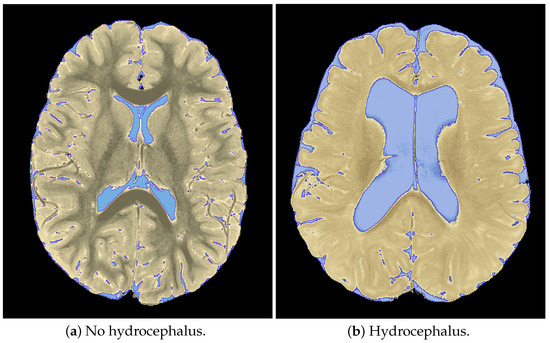

2.4. Subjective Hydrocephalus Rating